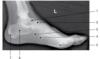

The radiograph shown in Figure 2–15 demonstrates the articulation between the

The radiograph shown is that of a medial oblique foot. With the foot rotated medially so that the plantar surface forms a 30-degree oblique with the IR, the sinus tarsi, the tuberosity of the fifth metatarsal, and several articulations should be demonstrated—the articulations between the talus and the navicular, between the calcaneus and the cuboid, between the cuboid and the bases of the fourth and fifth metarsals, and between the cuboid and the lateral (third) cuneiform.